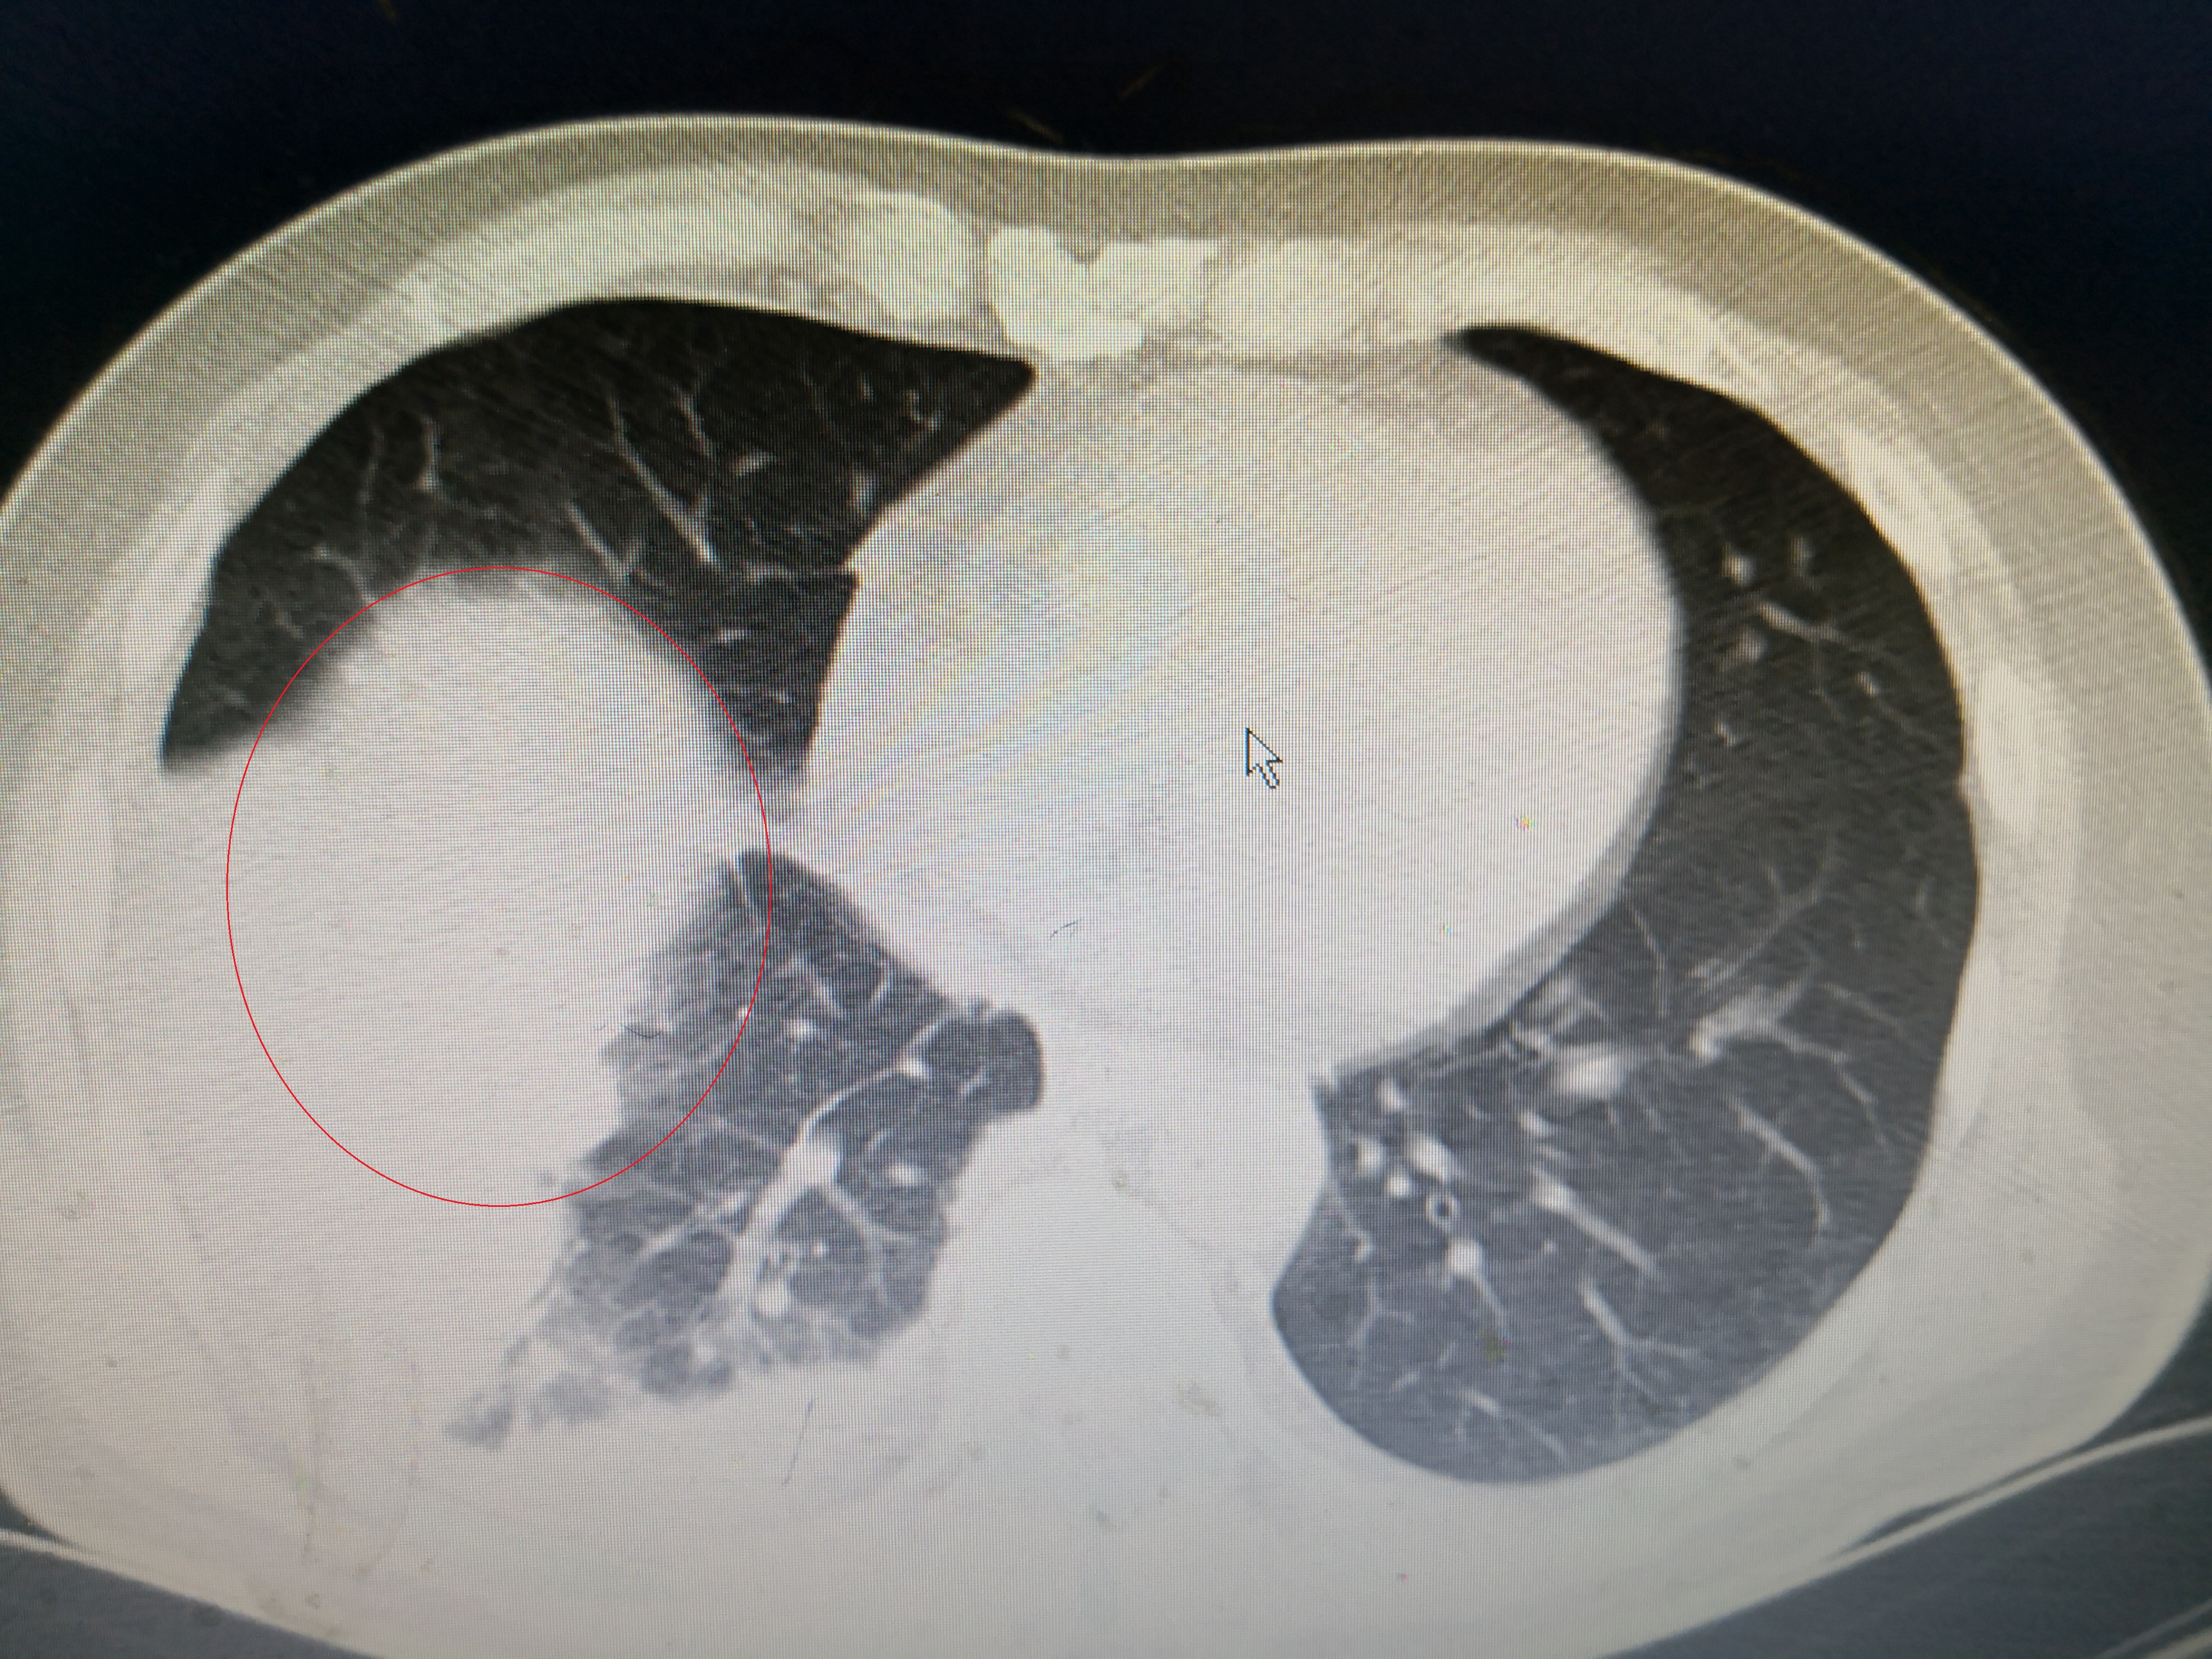

第一次氧分压降低

入院给予吸氧,喹诺酮+头孢二代标准抗感染方案,化痰治疗。通过5天治疗患者体温正常,不再咳嗽,精神状态好转,白细胞降到12.1×10^9,C反应蛋白降到46mg/l。氧分压90mmHg,恢复正常。该患者有顽固性呃逆,考虑和肺炎刺激膈肌有关,通过针灸、中药和口服巴氯芬治疗,也基本缓解。估计还有一周应该可以治愈出院。